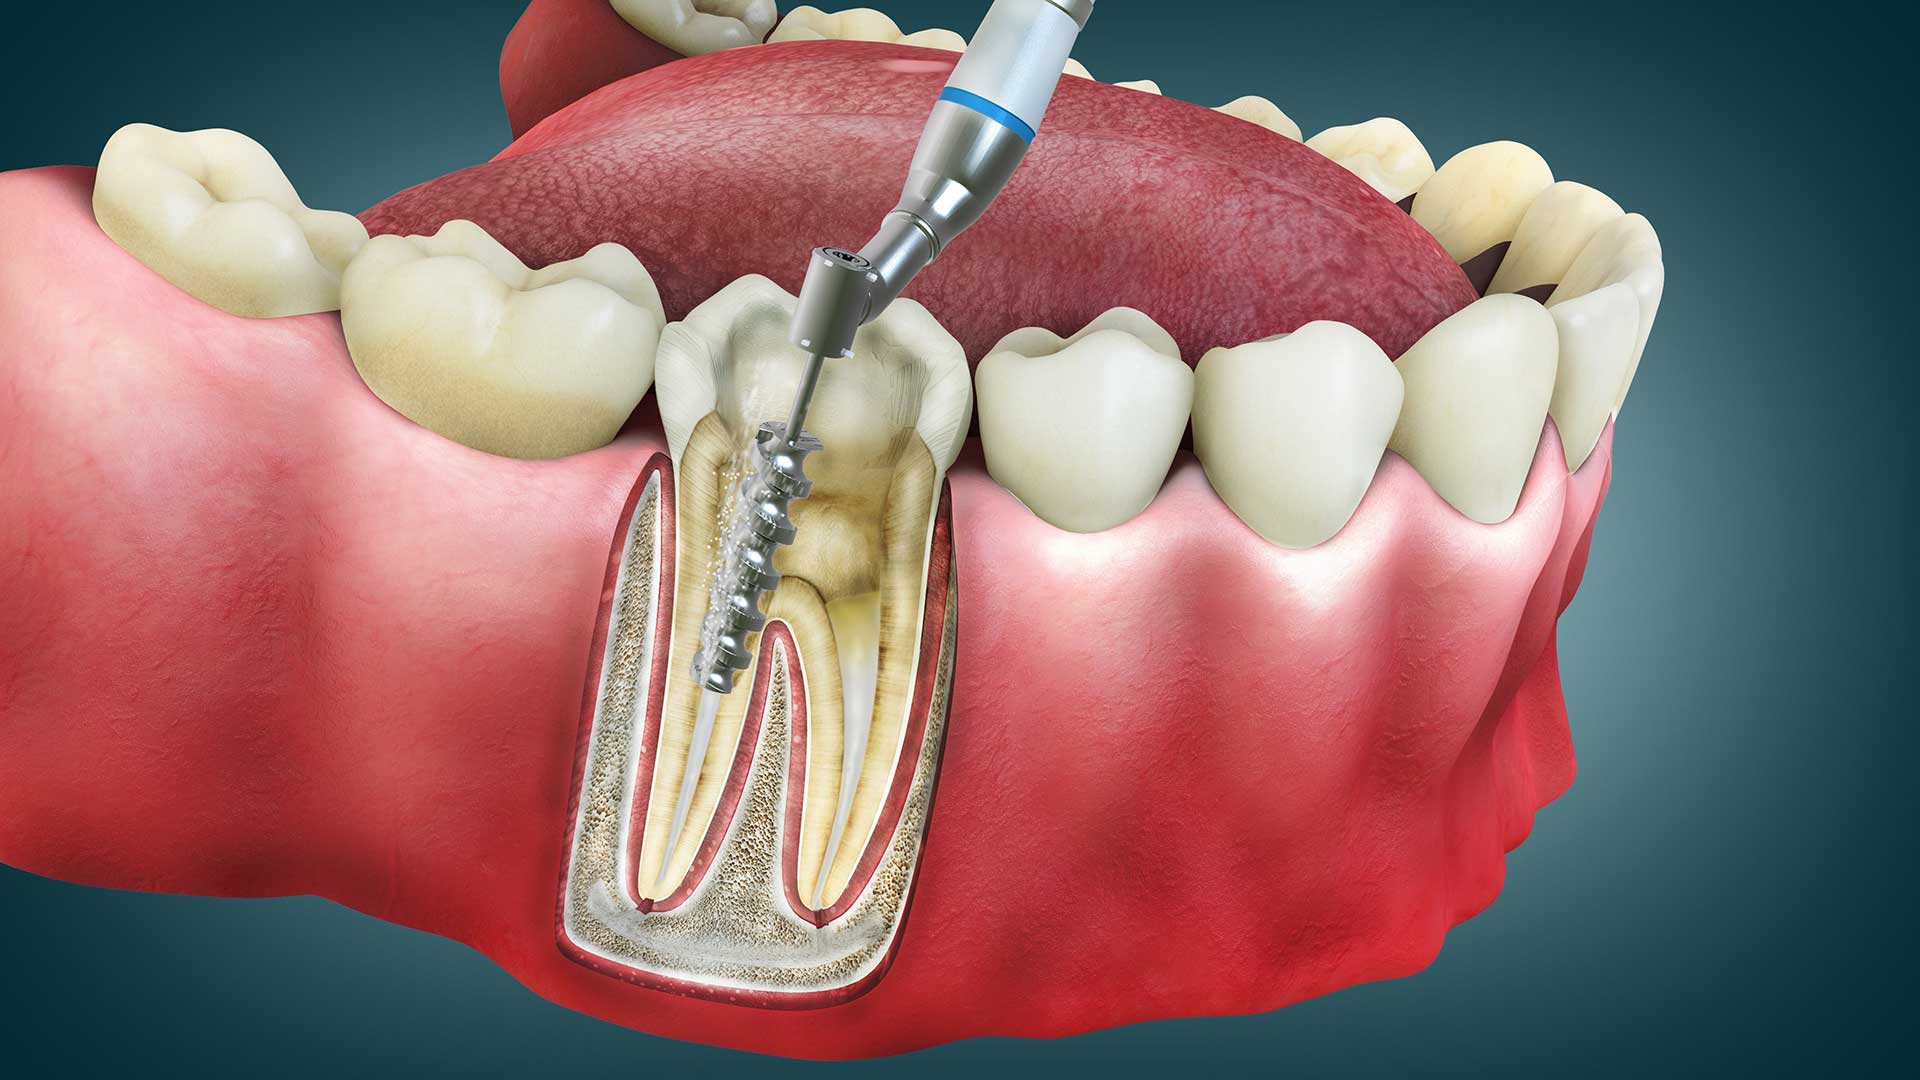

Root canal treatment (endodontic therapy) is a dental procedure designed to save a severely damaged or infected tooth by removing the infected pulp from inside the tooth's root canals.

The pulp contains nerves, blood vessels, and connective tissue. When this becomes infected due to deep decay, cracks, or trauma, it can cause severe pain and lead to abscesses if left untreated.

During the procedure, your endodontist carefully removes the infected pulp, cleans and disinfects the inside of the tooth, then fills and seals the space to prevent further infection.

4. Access Opening

A small access hole is drilled in the crown of the tooth to reach the pulp chamber. This opening provides access to the infected or inflamed pulp tissue.

5. Pulp Removal and Cleaning

The infected or inflamed pulp is carefully removed using specialized endodontic files. The root canals are thoroughly cleaned, shaped, and disinfected to eliminate all bacteria.

6. Filling and Sealing

The cleaned canals are filled with a biocompatible material called gutta-percha and sealed with adhesive cement to prevent future bacterial invasion.